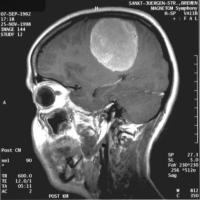

Aneurysma Hirntumor Bandscheibenvorfall

Aufgabe der Neurochirurgie ist die operative Behandlung der somatischen Erkrankungen des Zentralnervensystems und seiner Hüllen. Von Neurochirurgen werden Operationen an Gehirn, Rückenmark, peripheren Nerven sowie Schädel und Wirbelsäule durchgeführt. Solche Eingriffe sind unter anderem erforderlich bei allen Arten von Tumorerkrankungen, Unfallfolgen oder angeborenen Fehlbildungen von Gehirn und Rückenmark. Auch entzündliche Erkrankungen des Zentralnervensystems und spontan auftretende Blutungen infolge von Gefäßmissbildungen (Aneurysmen, Angiome) oder Schlaganfällen gehören zum Aufgabengebiet der Neurochirurgie. Ein weiterer Schwerpunkt ist die Behandlung degenerativer und traumatischer Wirbelsäulenprozesse, hier in erster Linie die Operation von Bandscheibenvorfällen sowie die operative Versorgung von Verletzungen der Wirbelsäule und des Rückenmarks. Nicht zuletzt werden auch Schmerzpatienten (z. B. bei Tumorerkrankungen, Trigeminusneuralgie, usw.) behandelt.